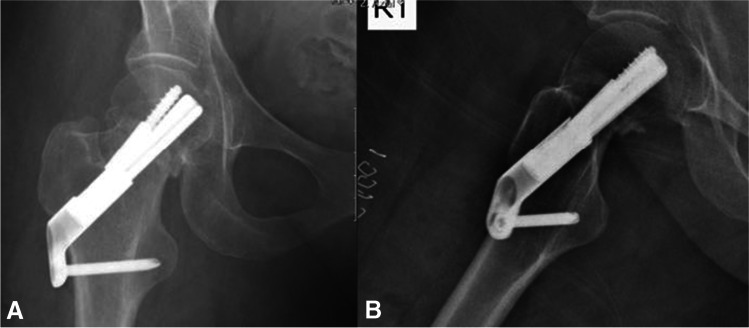

Fig. 7.

A, B AP and lateral radiographs showing right intracapsular femur fracture of a 71-year-old female. An isolated injury to the right hip after falling from own height when getting out of bed. Past medical history consists of chronic lymphocytic leukaemia, walks unaided

Fig. 8.

A, B AP and lateral radiographs postoperative day 1, demonstrating fixation of the fracture with FNS

Fig. 9.

A, B AP and lateral radiographs from last follow-up, 24 months after the surgical treatment. Walks unaided, no complaints of chronic hip pain